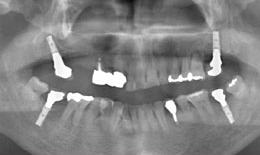

インプラント症例(5) 58歳 男性

インプラント フィクスチャー4本 285,000×4=1,140,000円(税抜)

上部構造

(ハイブリッドクラウン)4本

135,000×4=540,000円(税抜)

右上メタルボンドクラウン 97,000×3=291,000円(税抜)

1. 最初に右上の6番目の歯を抜きます。

2. 右上から、順番に7番目のところに、インプラントを入れていきます。

その上に歯を作り、しっかりとした四隅を作ります。